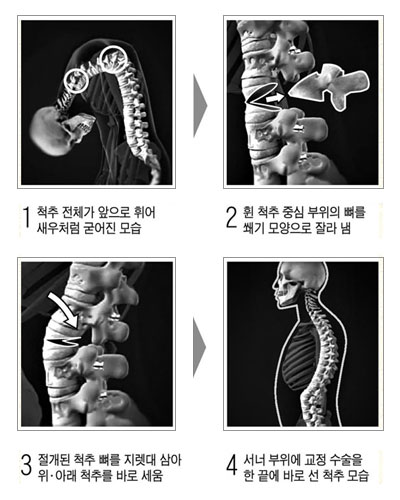

- 강직성 척추염

| |

척추의 관절이나 인대가 점차 골화하여 굳는 만성 염증성 질환으로

남성에게 많으며 15-30세의 유전적 소인이 있는 사람에게 흔히 나타납니다. 건이나 인대가

닿는 부위인 섬유성 조직과 뼈조직과의 연결부에 염증이 생기면 섬유염이 생기고 다시 골미란을

일으켜 골화가 진행됩니다.

자연스럽게 진행이 멈추는 경우도 있으나 대부분 수년에서 수십년 걸쳐 서서히 진행되어 목에서부터

허리아래까지 굳어지게 되는 경우가 많습니다. 증상은 하부요통에서 시작하며 초기엔 좌골신경통과

2)

치료

| |

- 통증 조절 ; 비스테로이드성 항염제, 항류마티스 약제등

- 운동 요법 ; 물리치료, 체조와 스트레칭, 수영등

- 수술적 치료 |